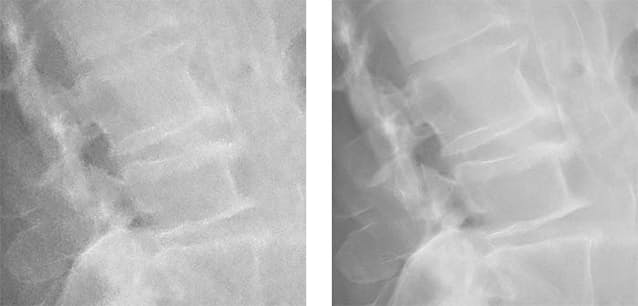

キヤノンは23日、X線撮影装置で撮影した画像のノイズを低減する画像処理技術を開発したと発表した。ディープラーニング(深層学習)を活用した独自の人工知能(AI)技術で、従来のノイズ低減処理に比べて最大で5割のノイズを低減できる。今後同社製のX線撮影装置のソフトウエア向けにオプションとして販売していく。

X線画像のノイズを低減する画像処理技術「Intelligent NR」を新たに開発した。キヤノン製のX線撮影装置で撮影した画像を表示するソフト向けのオプションとして販売する。これまで蓄積してきた臨床画像から約3000枚の X 線画像を選び、撮影部位ごとにノイズの特徴を機械学習した。画質を維持しながら、不要なノイズを効率的に除くことができるようになった。